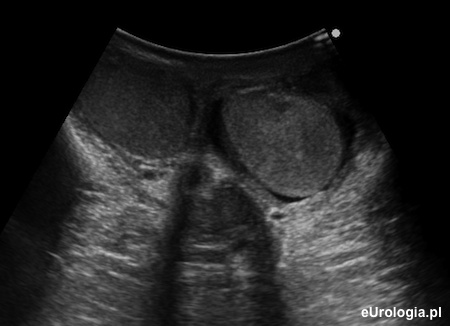

Fot. Obraz ultrasonograficzny prawidłowych jąder w mosznie.